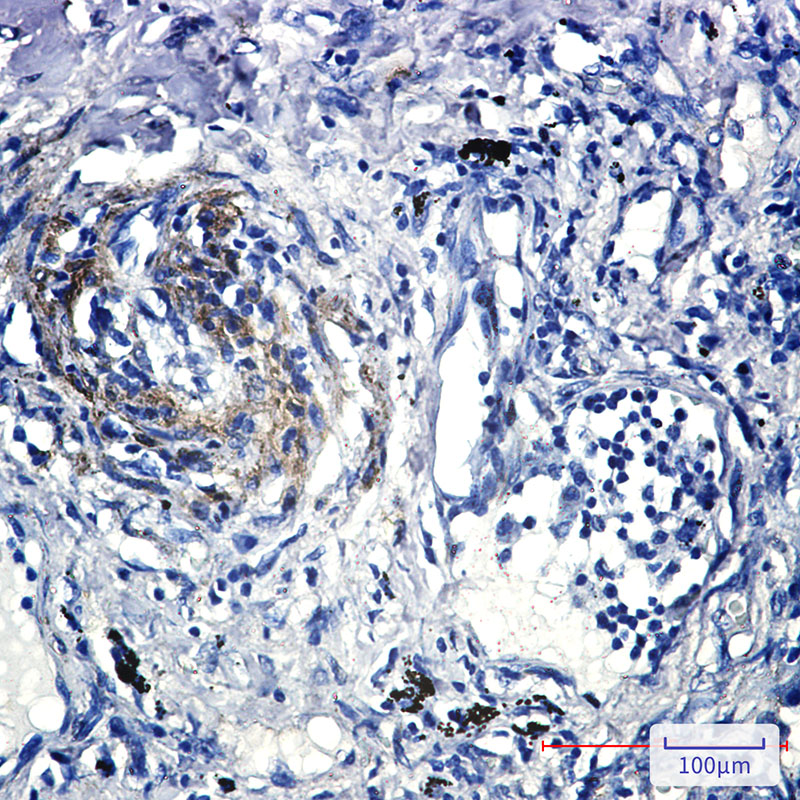

- Immunohistochemistry analysis of paraffin-embedded Human lung cancer tissue using Caveolin2 antibody. High-pressure and temperature Sodium Citrate pH 6.0 was used for antigen retrieval.